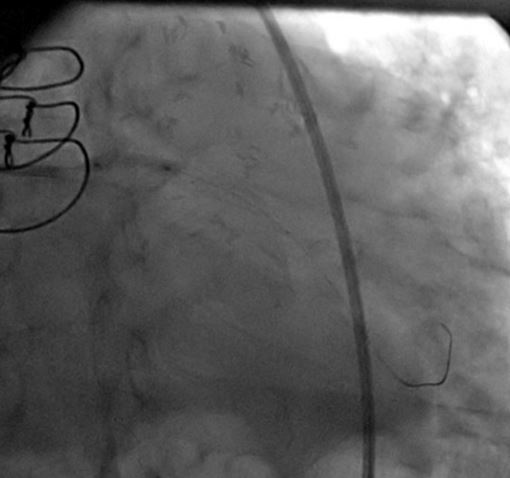

A CLs guiding catheter was used to engage the left coronary artery, and a Choicd floppy guidewire passed through the lesion. The lesion was predilated with a 1.5x15mm and 2x10mm Maveric balloon (figure 4). Then a 3.5x18mm Xience v stent was deployed at 16atm (figure 5, figure 6, figure 7). Post-dilation was done with a 4x10mm Firestar NC balloon (figure 8). The final result showed TIMI-III flow with no residual stenosis (figure 9).

The patient's hemodynamic and respiratory status improved, and he discharged home three days later.